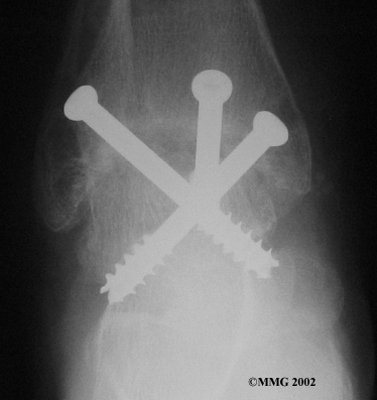

It is important when the surfaces are removed that the angles of the cut surfaces are correct. When the tibia is brought against the talus, the foot should be at a right angle to the lower leg. Once the cuts are made the bones must be held in place while they fuse. This can be done using large metal screws and metal plates if necessary. The screws are usually under the skin and are not removed unless they begin to rub and cause pain.

Inserting the screws

After ankle fusion, the physical therapists at FYZICAL Garland Campbell can help you learn to walk smoothly and without a limp. Although time needed for recovery varies among patients, an ankle brace will typically replace your cast after eight to 12 weeks. Your surgeon will take X-rays frequently to see if the bones are fusing together. You will probably need to use crutches during the time you wear the cast. As the fusion grows stronger, you will begin to put more weight on your foot when walking.